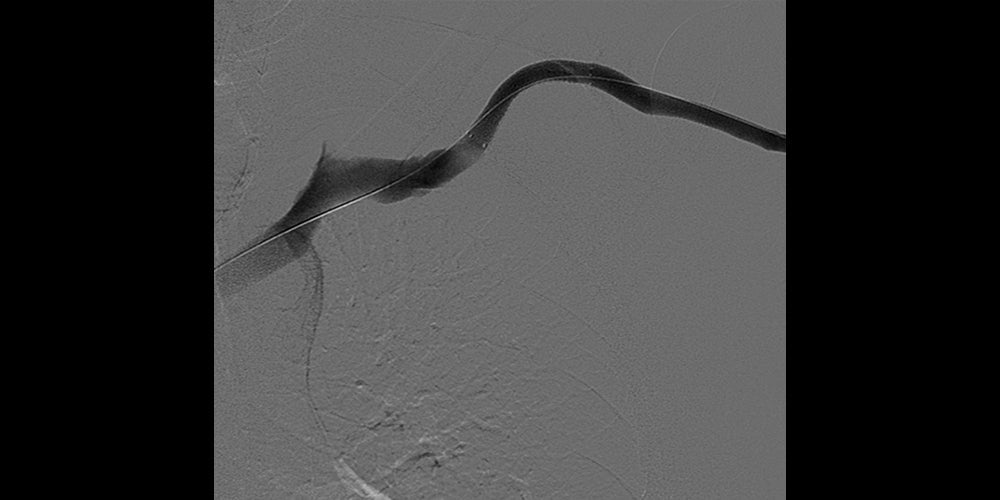

Direct left brachiocephalic fistula access. Venography demonstrated recurrent cephalic arch stenosis. Venoplasty to 7 mm with a high-pressure balloon and recoil stenosis. Upsizing of sheath access. Deployment of a 7 mm x 5 cm GORE® VIABAHN® Device, and post-dilatation.

- When venoplasty fails the GORE® VIABAHN® Device offers a durable solution as it conforms very well to the anatomical configuration of the arch without kinking

- It is possible to accurately deploy a GORE® VIABAHN® Device in the cephalic arch without significant compromise to the axillary vein